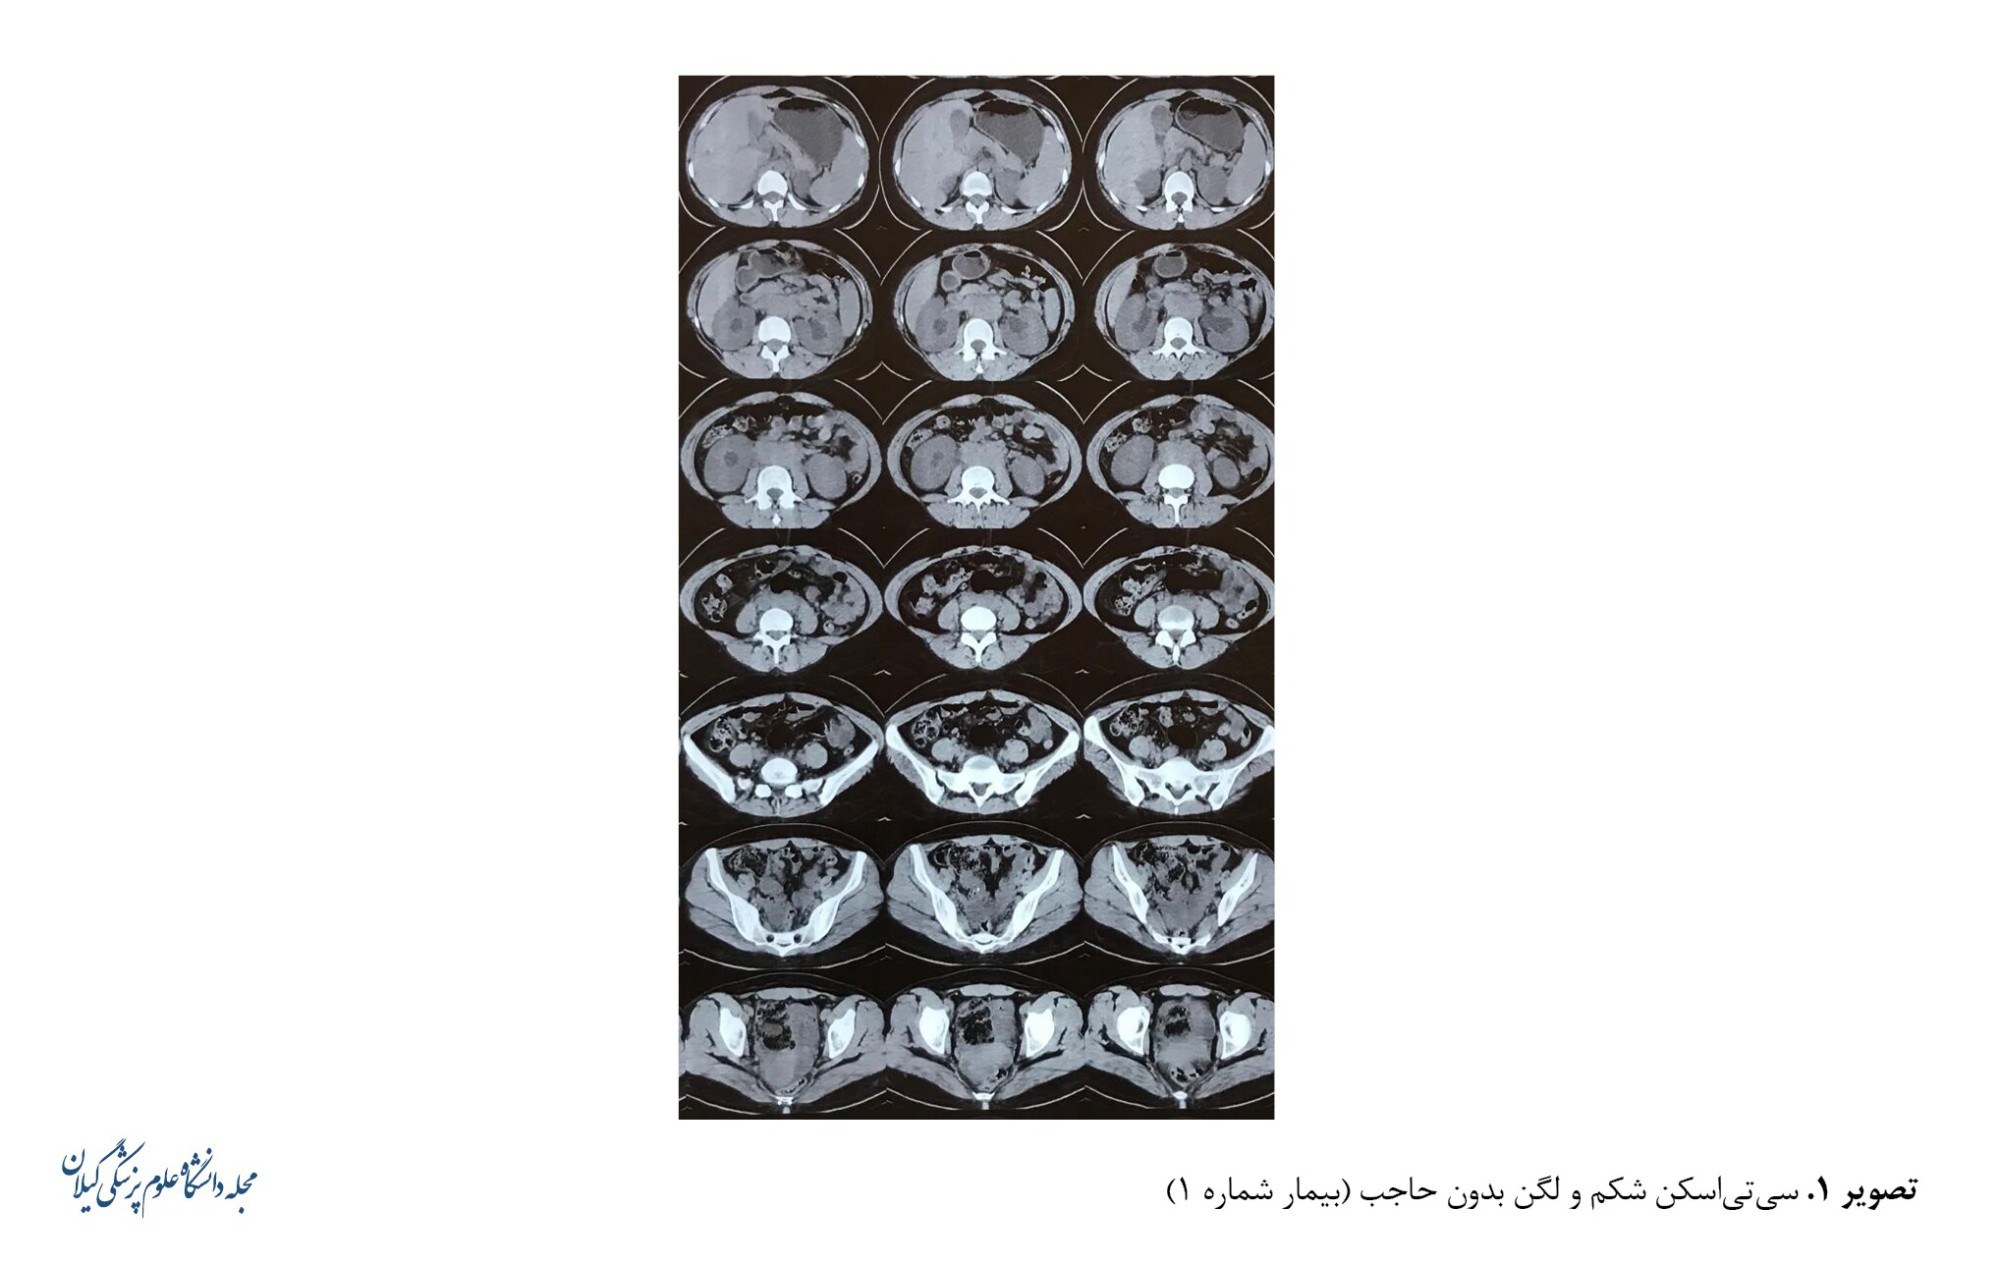

در بررسی آزمایشگاهی، شمارش کامل خون، نرمال؛ سرعت رسوب گلبول قرمز، 40 میلی‌متر بر ساعت؛ پروتئین واکنشگر C، 10 میلی‌گرم در دسی‌لیتر؛ نیتروژن اوره خون ، 33 میلی‌گرم در دسی‌لیتر و کراتینین، 2/5 میلی‌گرم در دسی‌لیتر بود. در طول بستری برای بیمار سونوگرافی شکم و لگن انجام شد که در گزارش سونوگرافی، کبد، کیسه صفرا و پانکراس طبیعی بودند و اسپلنومگالی یافت نشد. هر دو کلیه بزرگ‌تر از حد طبیعی گزارش شد که سایز کلیه راست 47×147 میلی متر و کلیه چپ 47×130 میلی متر بود. اکو پارانشیمی هر دو کلیه نرمال بود و هیدرونفروز درجه 1 با اتساع حالب در هر دو طرف مشهود بود. همچنین تخمدان‌ها و رحم نرمال بودند. به دلیل هیدرونفروز در سونوگرافی، بیمار تحت سی‌تی‌اسکن بدون کنتراست شکم و لگن قرار گرفت که هیدرونفروز بدون وجود سنگ را در کلیه ها نشان داد. همچنین تراکم بافت نرم در ناحیه پاراآئورت به ابعاد 26×59×129 میلی‌متر مشاهده شد. لنفادنوپاتی چندگانه با حداکثر قطر ساژیتال شکمی 10 میلی‌متر در حفره شکمی مشاهده شد (تصویر شماره 1).